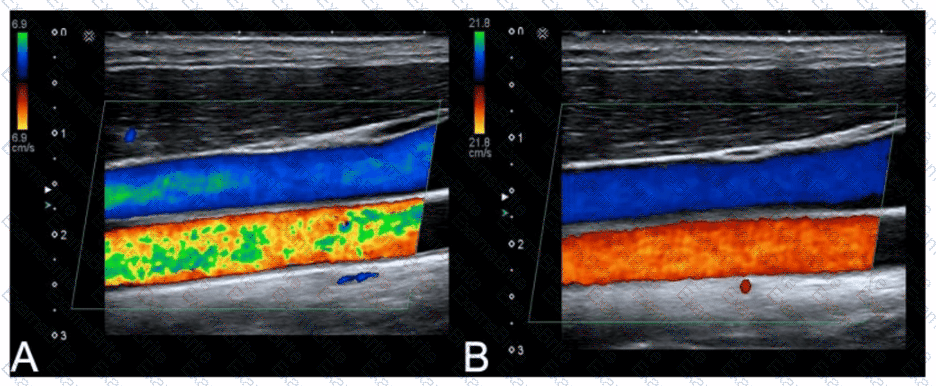

Questions 3

How can the spectral Doppler mirroring seen in this image be eliminated?

Options:

A.

Decrease wall filter.

B.

Decrease Doppler gain.

C.

Increase dynamic range.

D.

Increase pulse repetition frequency (PRF).

Discussion 0